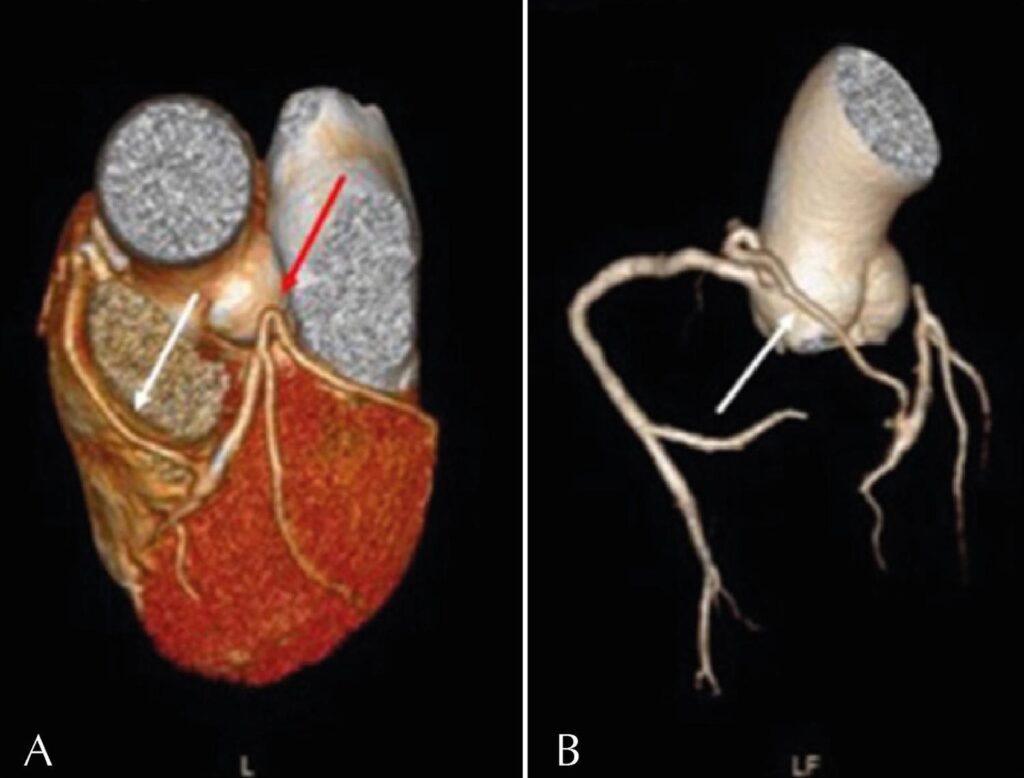

Rare Incidental Finding on Coronary Artery CT Angiography: Left Main Coronary Artery Atresia

Congenital left main coronary artery atresia (CLMCAA) is a coronary anomaly in which the left coronary ostium or trunk is absent. The anterior descending (AD) and circumflex (CX) arteries are usually connected and proximally end blindly. Left chamber perfusion is provided by the right coronary (RC) collaterals. It is the rarest coronary anomaly, with fewer than 70 cases described in the literature. The clinical CLMCAA spectrum ranges from asymptomatic cases (due to an efficient collateral system) to symptoms such as angina, tachyarrhythmias, syncope, and sudden death., Surgical revascularization is recommended in symptomatic patients; however, preventive surgical treatment is controversial in asymptomatic patients without inducible myocardial ischemia.–